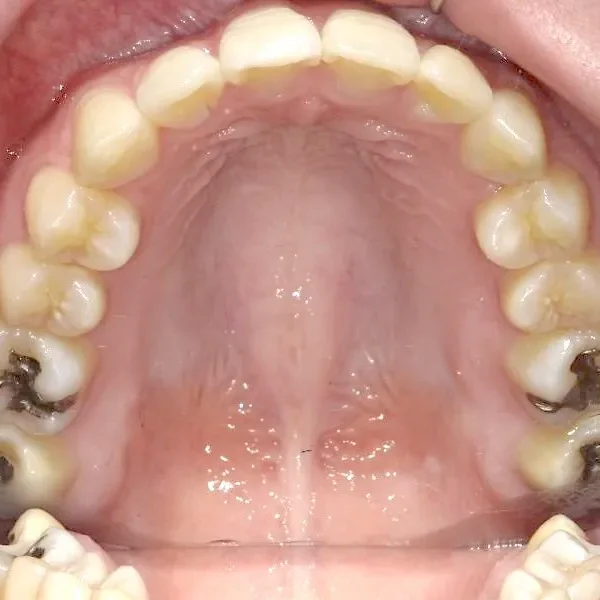

治療回数○回、2年9ヶ月の治療期間で矯正治療を終了しました。

主訴が改善され、ご満足頂きました。

治療経過1